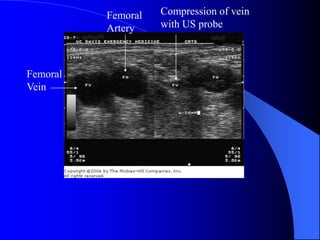

Ultrasound-Guided Central

Venous Access

 Becoming standard of care

 Vein is compressible

 Vein is not always larger

 Vein is accessed under direct

visualization

 Helpful in patients with

difficult anatomy

Femoral

Vein

Artery

Compression of vein

with US probe